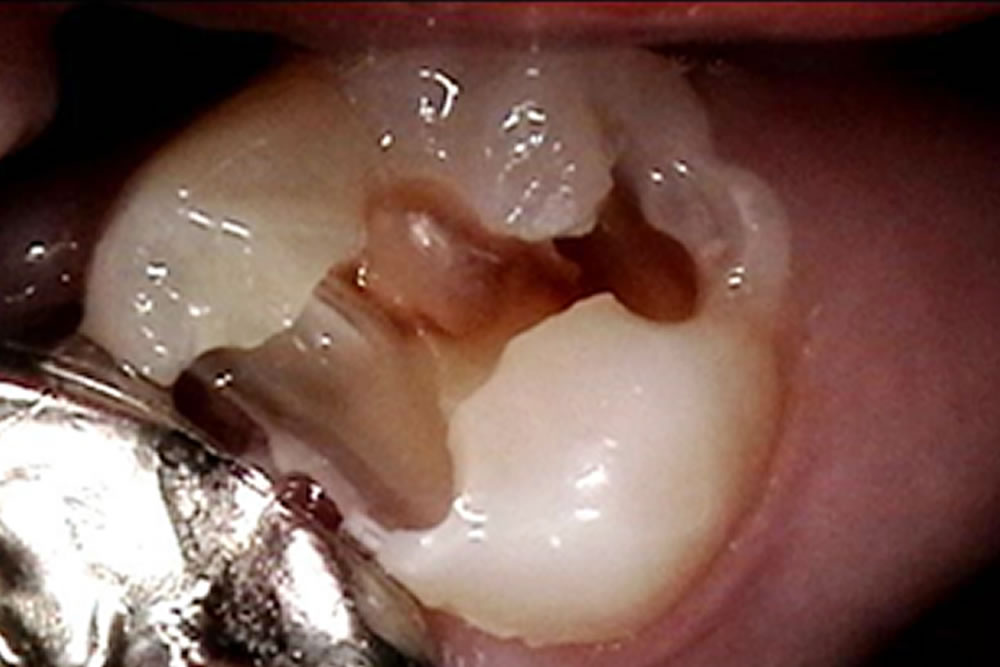

再発した銀歯の虫歯治療後にセラミックで修復した症例

再発した銀歯の虫歯治療後にセラミックで修復した症例 メンテナンスの際、レントゲンを撮影し、左下6番目の歯の銀のつめ物の下で虫歯になっていることが分かりました。 患者さまに説明し、治療をすることとなりました。 銀歯の除去・ […]